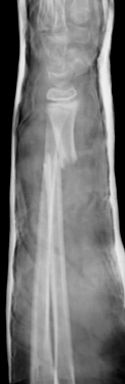

En las fracturas de antebrazo no es infrecuente la presencia de lesiones asociadas. Se debe sospechar siempre que exista una fractura aislada de un hueso del antebrazo. La más frecuente es la fractura luxación de Monteggia, cuando en una fractura proximal de cúbito se asocia una luxación de la cabeza radial. En algunos casos, la fractura de cúbito puede ser una deformidad plástica que a menudo pasa desapercibida. El tratamiento consiste en la reducción de la cabeza radial y la estabilización de la fractura de cúbito en los casos agudos, mediante inmovilización en niños pequeños y osteosíntesis en niños mayores (Figura 16).

Figura 16: a- Imagen radiológica donde se aprecia una luxación de la cabeza radial asociada a una fractura del tercio medio-proximal del cúbito. b- reducción y osteosíntesis con aguja de Kirschner intramedular y reducción de la cabeza radial.